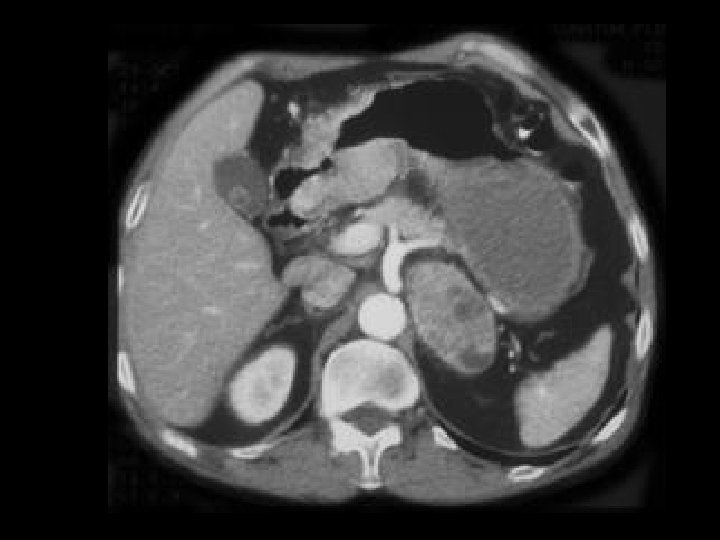

Pancreatic pseudocysts • Findings: – Multiple large pancreatic cystic lesions • ddx: – Von-Hippel Lindau – Cystic pancreatic neoplasm